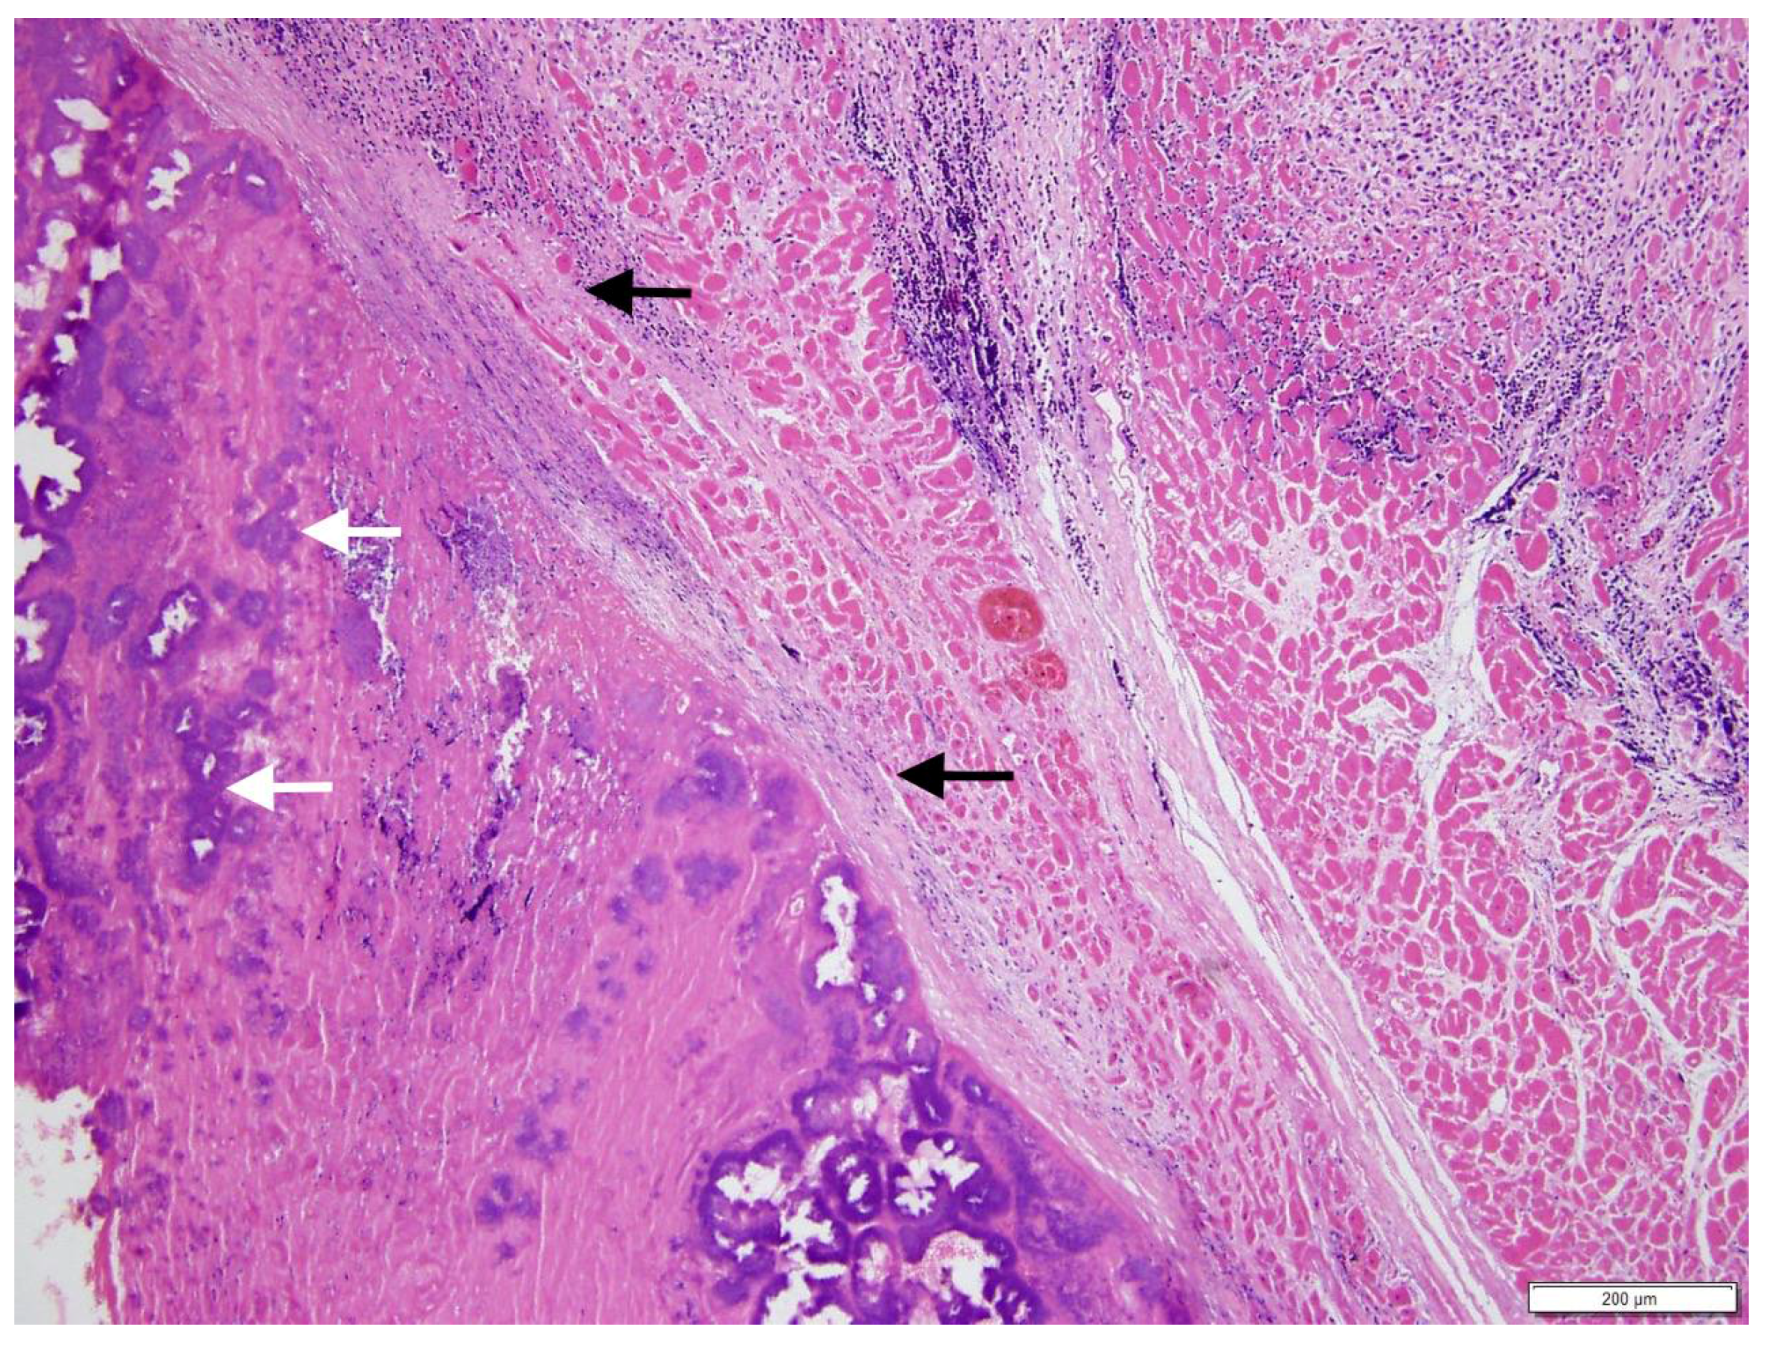

A necropsy revealed a severe, fibrino-necrotic, vegetative mitral, aortic and tricuspid valve endocarditis (Figure 3A,B), with milder lesions on the tricuspid valve. A severe, unilateral, fibrino-suppurative, and haemorrhagic mastitis of the right udder, with severe, diffuse supra-mammary lymphadenitis, was also identified. There was moderate segmental enteritis and mild bronchopneumonia. Samples were collected for histopathology, and pericardial fluid and a fine needle aspirate, from the udder, were collected for cytology. Blood from the LV and secretions from the udder, as well as a section of the aortic valve, were collected for culture and sensitivity. The cytology for the pericardial fluid was consistent with acute haemorrhage. The cytological report for the secretion from the udder supported gross pathologic findings of a septic suppurative inflammation. On histological examination, the endocardium was multifocally effaced, with large attached masses of fibrin and necrotic debris, containing multiple bacterial colonies composed of gram-positive cocci forming groups. These areas were variably separated from underlying myocardium by a zone of granulation tissue and fibrosis, which extended into the myocardial interstitium separating the cardiomyocytes (Figure 4). Enzootic calcinosis was ruled out due to a lack of substantive gross and histopathologic findings. There was no colony growth for the vegetative lesion of the aortic valve or the blood from the LV. A culture of the secretions from the udder was performed following standard protocols for bacteriological culture. Briefly, isolates were placed on blood and MacConkey agar, colonies were subsequently Gram stained, and catalase and coagulase tests were performed. The culture results revealed catalase and coagulase positive Staphylococcus sp. growth, which was resistant to tetracycline, penicillin, and streptomycin.

Figure 4. Effaced endocardium with attached fibrinonecrotic mass, containing bacterial colonies (white arrows), and separated from underlying myocardium by a zone of granulation tissue and fibrosis, which disrupts the cardiomyocytes (black arrows). H&E stain, magnification 10×.